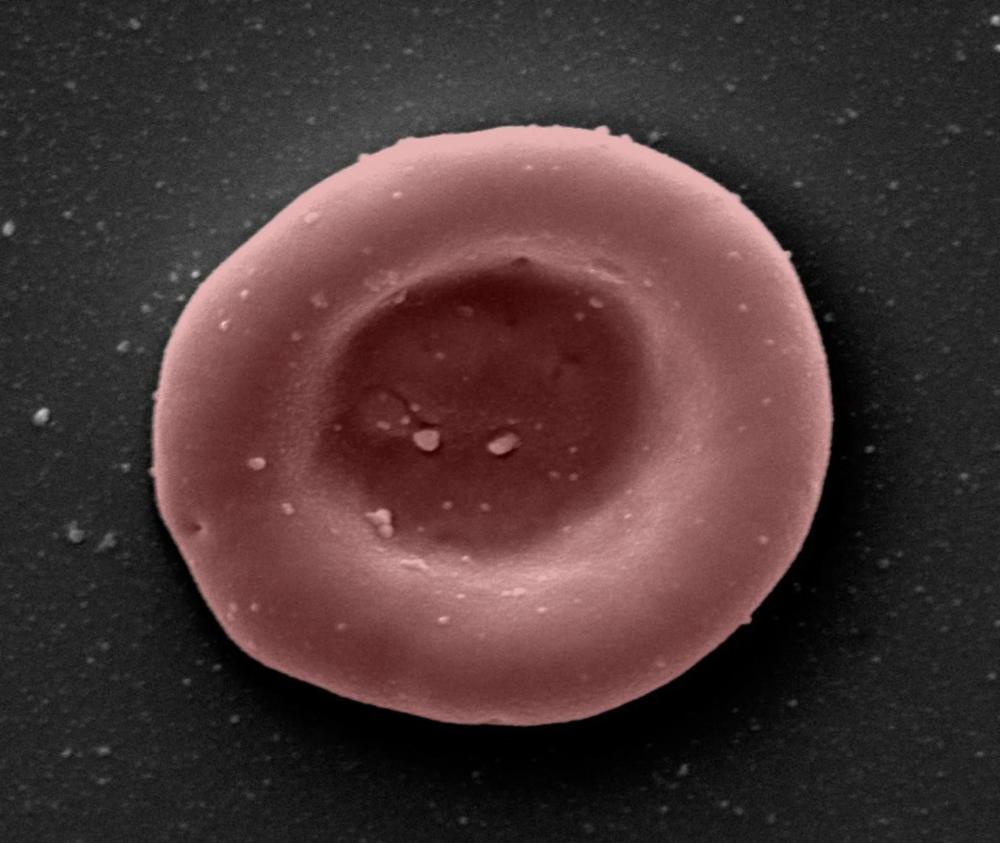

上图:在实验室中生长的红血球的显微镜图像。

英国国家医疗服务体系(National Health Service)在一项临床试验中首次向人类患者输血了实验室培育的干细胞。这不仅打开了通过消除对捐赠者的需求来缓解血液短缺的前景,而且还可能导致对难以找到相容捐赠者的疾病进行更好的治疗。